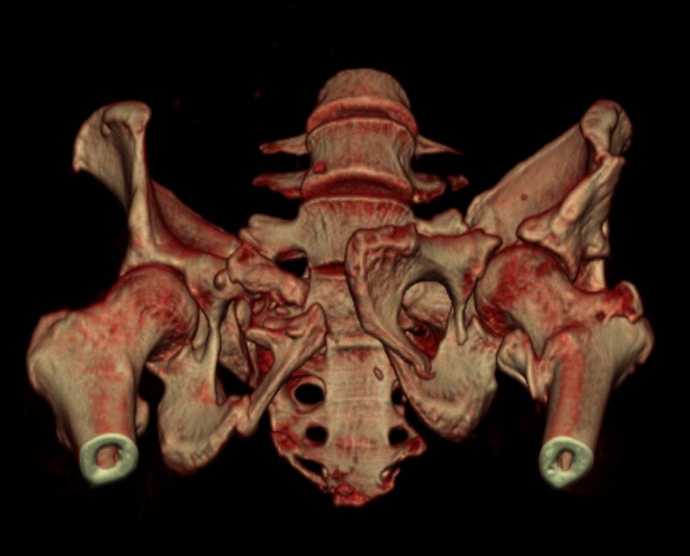

Больная 43 года (промышленный альпинист), 28.07.08 в результате падения с 5 этажа получила политравму: Перелом свода и основания черепа. Вертикально-нестабильное повреждение таза, осложнённое разрывом мочевого пузыря. Чрезвертельный перелом левого бедра. Перелом правой таранной кости, переломовывих правой кубовидной кости. Тупая травма живота, разрыв печени, ушиб почек. Забрюшинная гематома. В день травмы - лапаротомия, ушивание ран печени. Разрыв мочевого пузыря не диагностирован. Течение болезни осложнилось развитием мочевого затёка и обширной пред- и забрюшинной флегмоны, сформировался свищ мочевого пузыря. 19.8.2008 вскрытие, дренировние флегмоны, ревизия мочевого пузыря, обтурация мочевого свища (свищ закрылся в октябре), 1.10.2008 некрэктомия, пластика по Шеде-Лидскому правой кубовидной кости. По результатам КТ диагностирован рак правой почки (диагностическая находка), 8.10.2008 нефрэктомия справа. Переломы велись консервативно. Имеется вертикальное смещение левой половины таза с выраженным отведением крыла (клинически подвижности нет), несросшийся низкий двухколонный перелом левой вертлужной впадины с потерей конгруэнтности, укорочение около5 см, застарелый разрыв лонного сочленения, неправильно сросшиеся переломы обеих ветвей правой лонной кости с укорочением, патологическая подвижность лоно-седалищного фрагмента слева. Правая нижняя конечность неопорна, несмотря на то, что лежа прямую ногу поднимает, ходит на левой ноге (ортопедическая обувь) с костылями, справа тазобедренный ортез. Седалищные нервы работают.Урологи отпустили больную на 6 мес.

Извиняюсь, ошибся : опорная нога у больной правая. Левая нога неопорная, т.к. сращения на уровне бедра и вертлужной впадины нет.